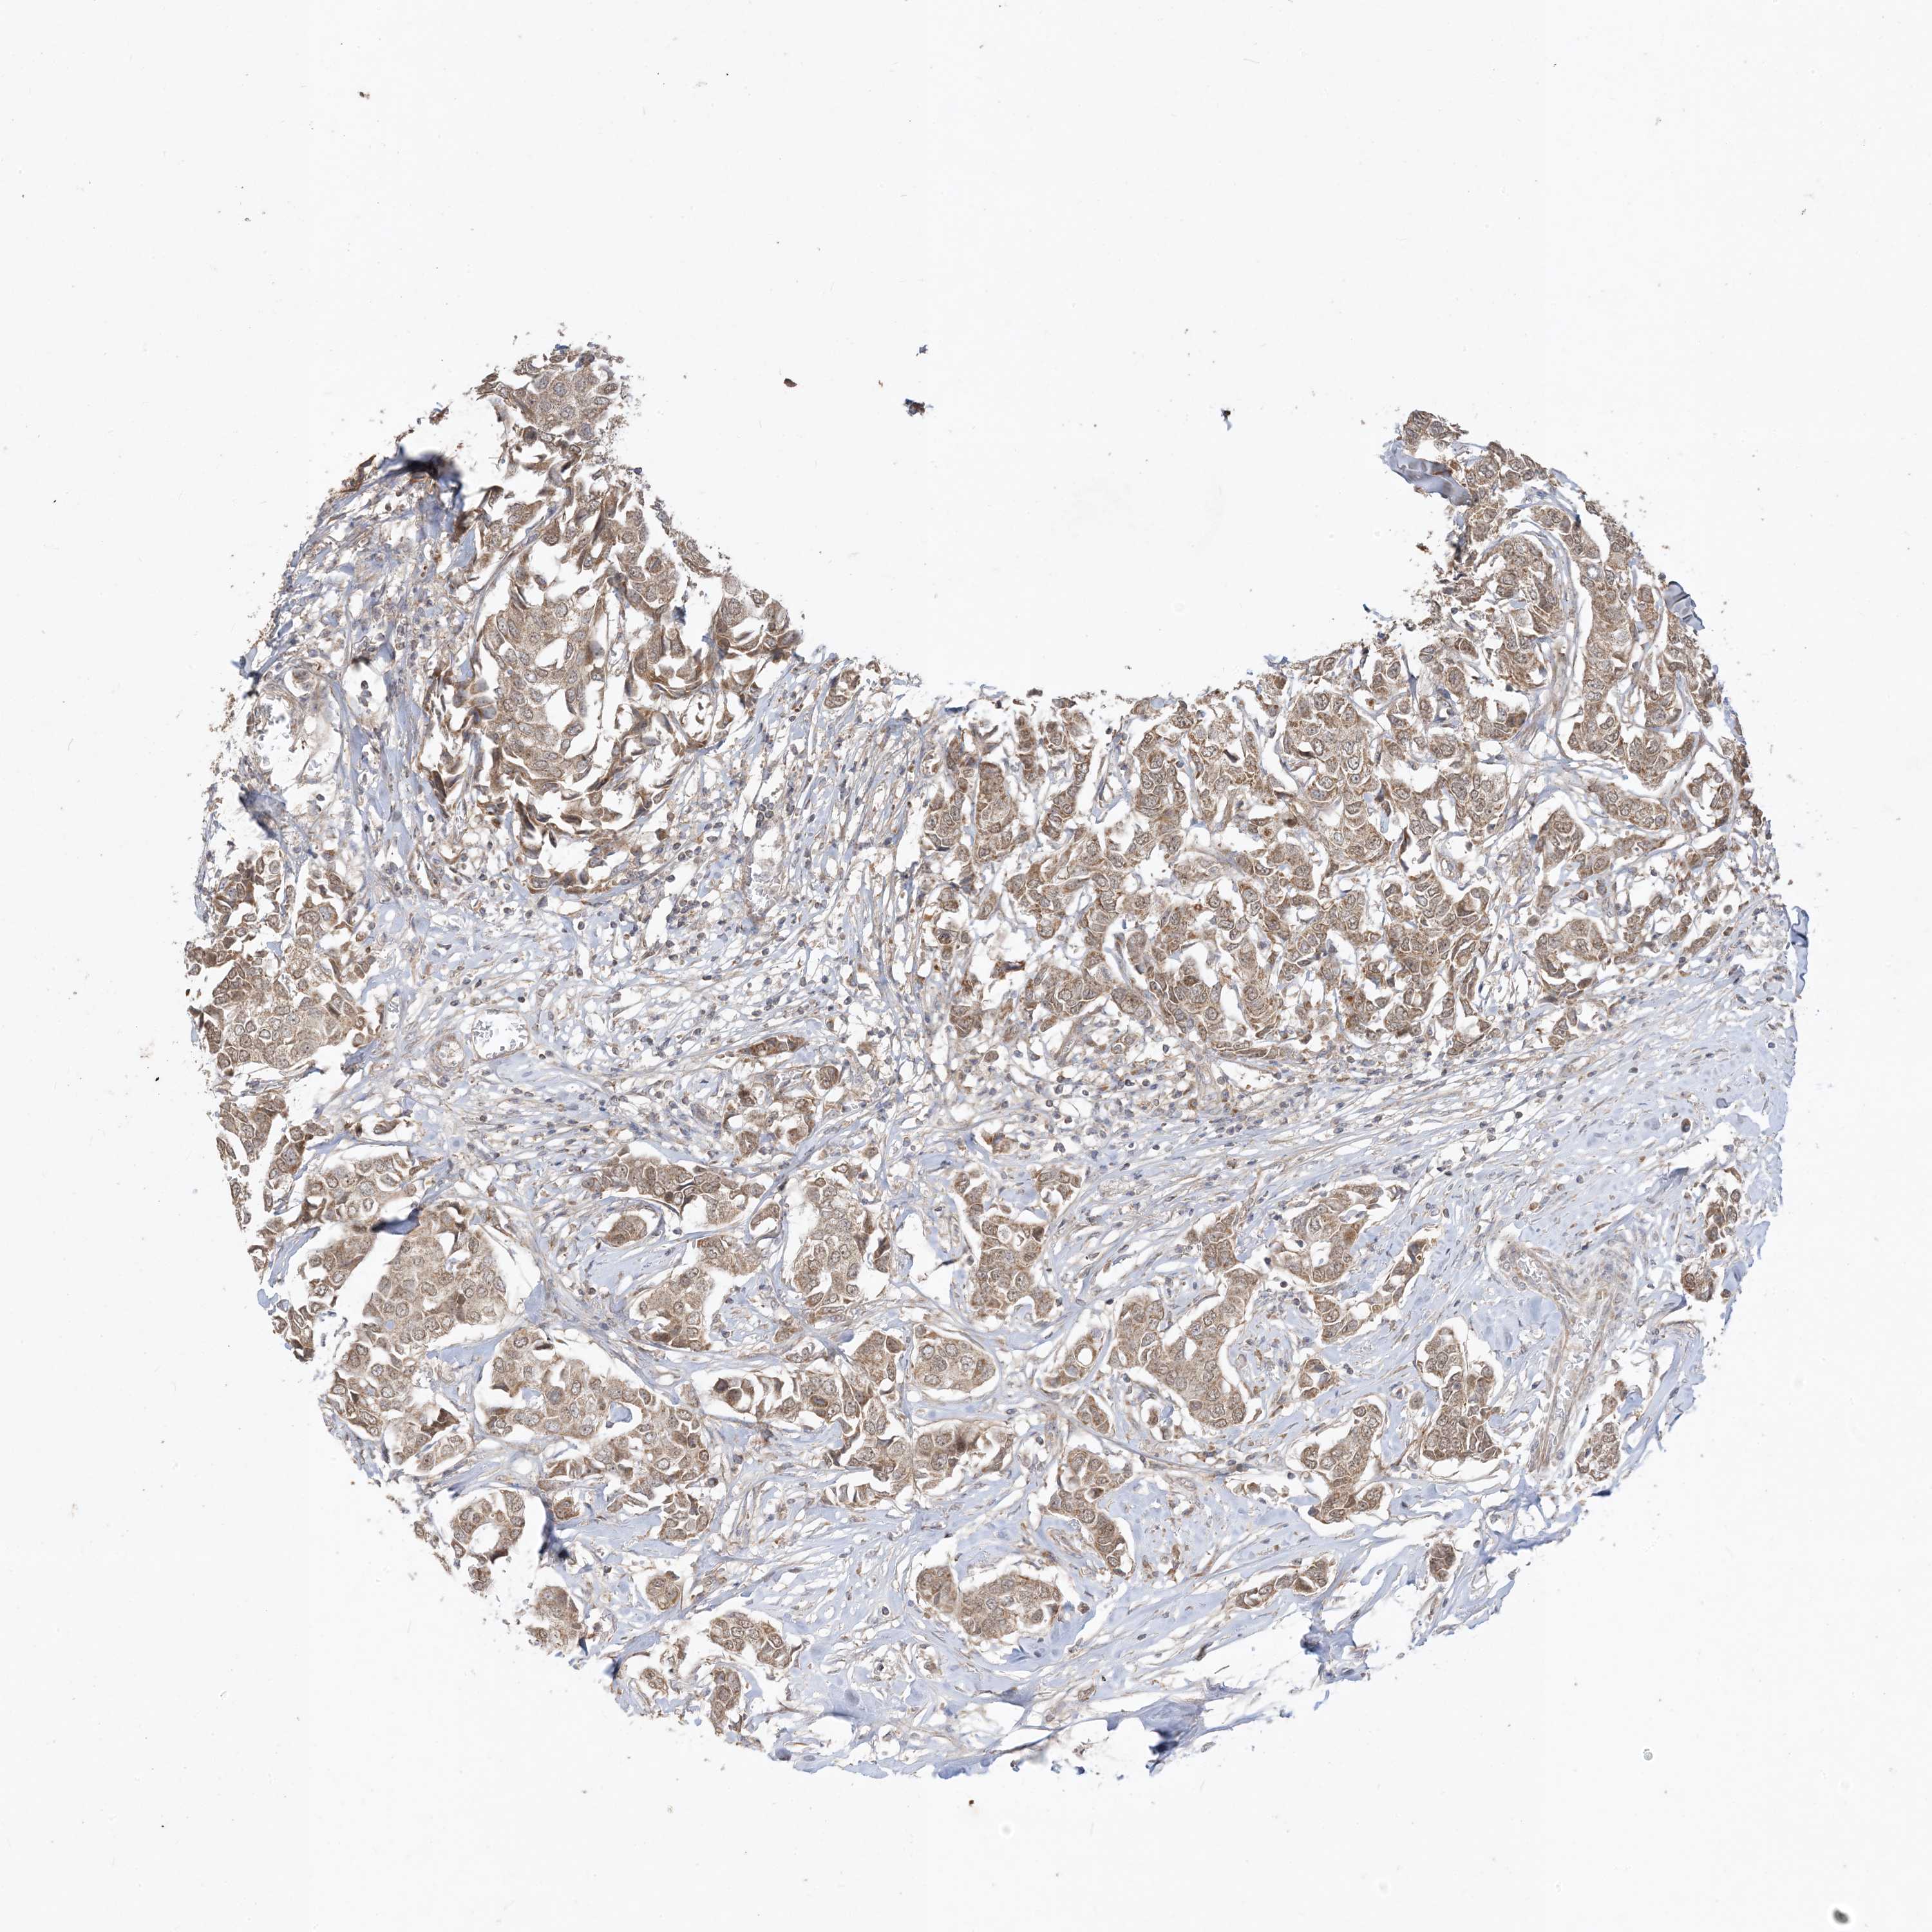

CANCER BREAST CANCER Show tissue menu

BRCA TCGA BRCA VALIDATION PROTEIN EXPRESSION